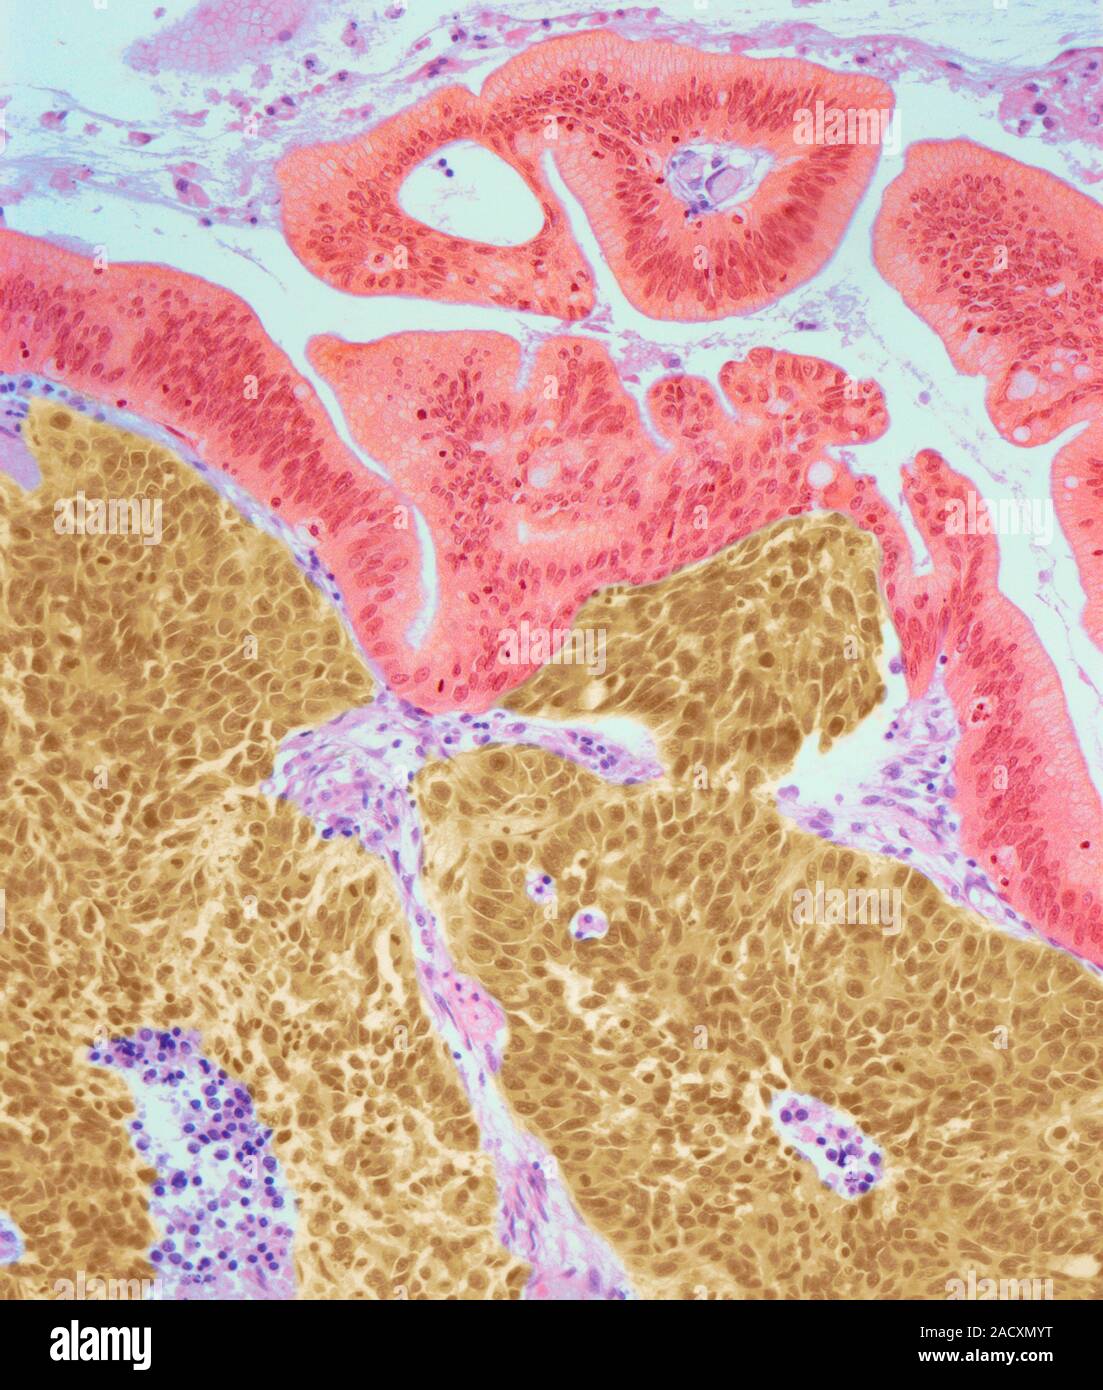

From www.alamy.com

Cervical cancer. Light micrograph (LM) of a section of a large cell Neuroendocrine Cancer Cervix Neuroendocrine carcinoma of the cervix (necc) is a rare variant of cervical cancer. Neuroendocrine carcinoma of the cervix (necc) is a rare variant of cervical. This study aims to investigate the. Aims neuroendocrine carcinoma of the cervix (necc) is a rare variant of cervical cancer. Cervical small cell neuroendocrine carcinoma (scnec) is a rare invasive cancer, accounting for no more. Neuroendocrine Cancer Cervix.

Cervical cancer. Light micrograph (LM) of a section of a large cell Neuroendocrine Cancer Cervix Neuroendocrine carcinoma of the cervix (necc) is a rare variant of cervical cancer. Neuroendocrine carcinoma of the cervix (necc) is a rare variant of cervical. This study aims to investigate the. This topic review will cover the epidemiology, clinical presentation, staging, and treatment of small cell neuroendocrine. 2 3 the 2014 world health organization (who) clas. This study aims to. Neuroendocrine Cancer Cervix.

Cervical cancer. Light micrograph (LM) of a section of a large cell Neuroendocrine Cancer Cervix Neuroendocrine carcinoma of the cervix (necc) is a rare variant of cervical. Aims neuroendocrine carcinoma of the cervix (necc) is a rare variant of cervical cancer. This topic review will cover the epidemiology, clinical presentation, staging, and treatment of small cell neuroendocrine. This study aims to investigate the clinicopathological features. 2 3 the 2014 world health organization (who) clas. Neuroendocrine. Neuroendocrine Cancer Cervix.